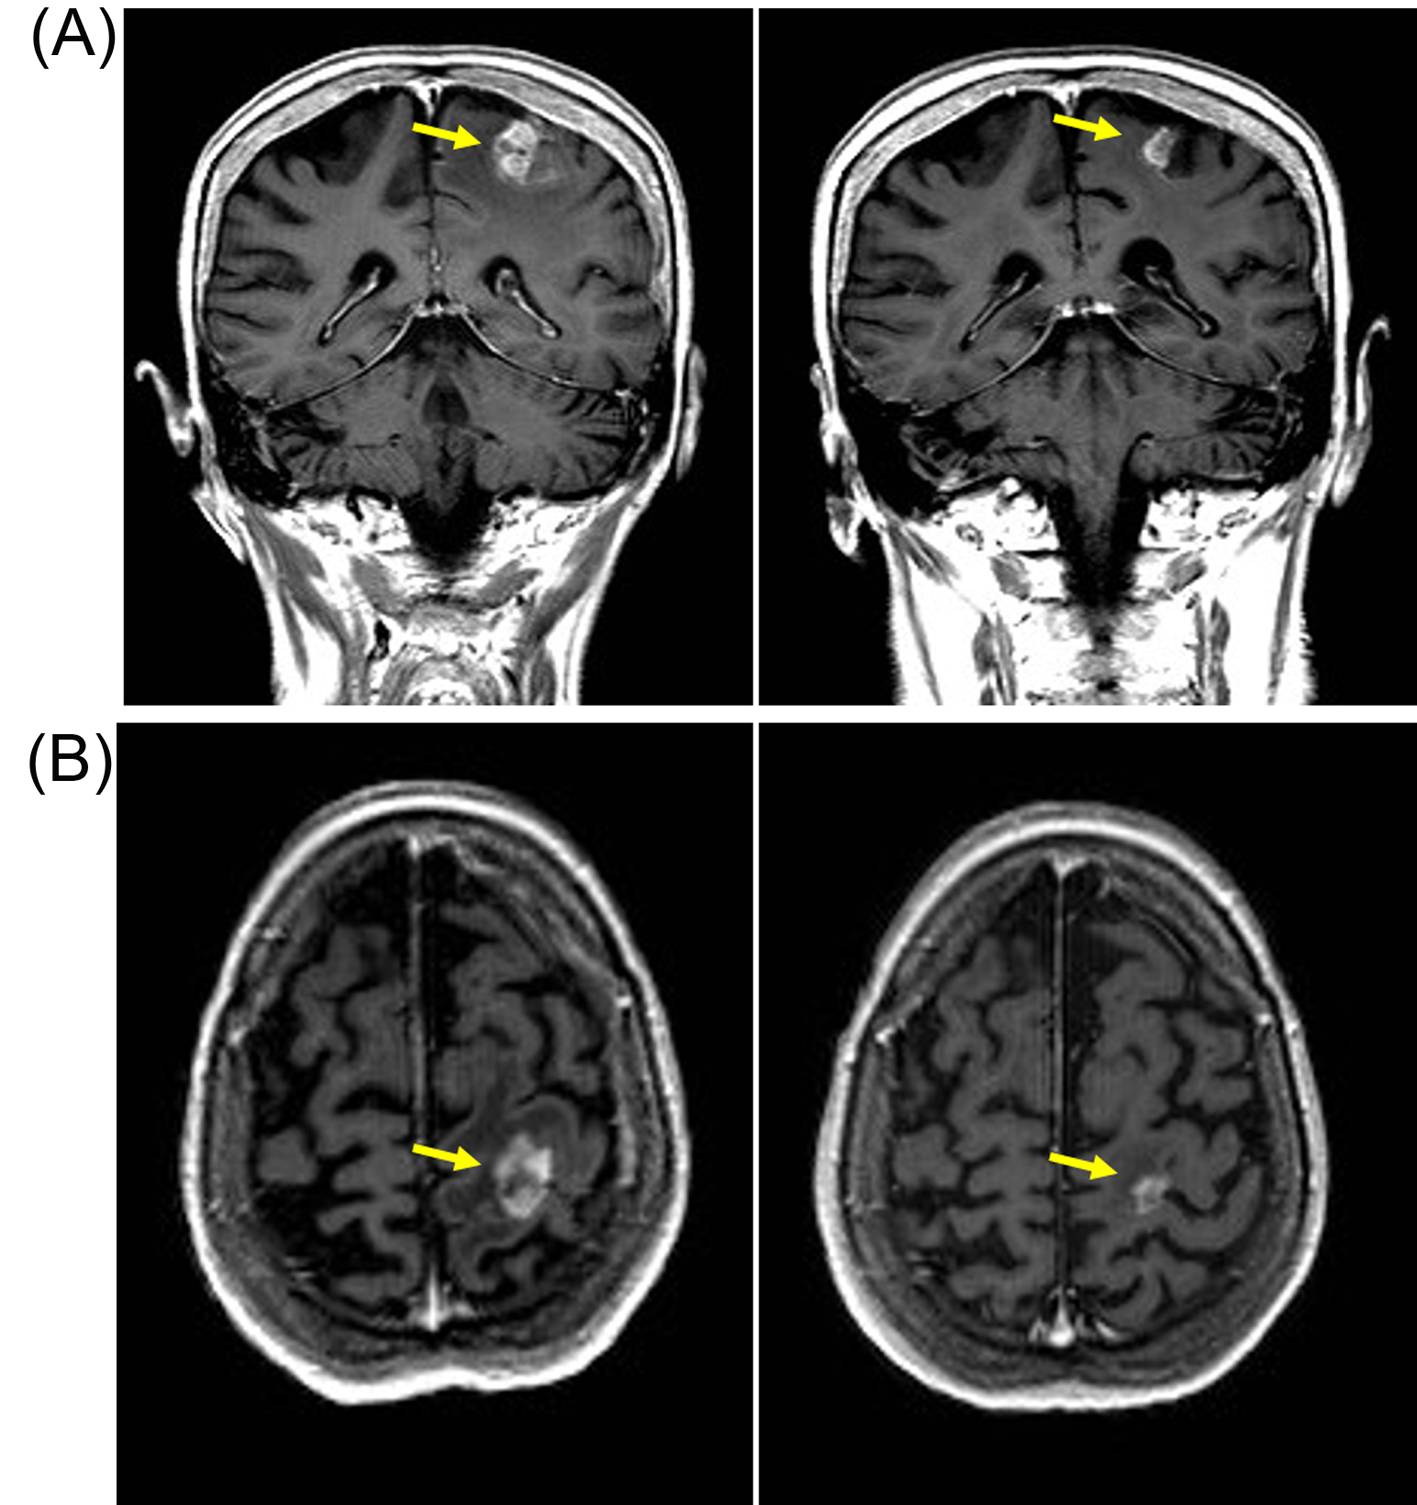

In June 2011 a follow-up CT showed small volume lung metastasis and stable appearances of brain metastasis. There was an improvement in her clinical condition and performance status (WHO grade 1-2), but she had commenced therapeutic anticoagulation with low-molecular weight heparin in view of below-knee deep vein thrombosis and pulmonary embolism. In view of reappearance of lung metastasis, she was commenced on pazopanib 800 mg/day that she tolerated well with no significant toxicities. She underwent repeat imaging 3 months later that showed an improvement in lung metastasis and also response in the brain metastasis (Fig. 2). She continued on pazopanib 800 mg/day, but the dose was reduced to 600 mg/day in December 2011 in view of symptoms of poor appetite and fatigue. Despite the reduction in dose of pazopanib, she continued to have poor tolerance of subsequent cycles and she embarked on treatment “holiday” with discontinuation of pazopanib in March 2012. She had progression-free interval of 11 months, but in February 2013 she developed progressive brain metastasis with enlarging lesion in the left parietal lobe. She recommenced pazopanib at 600 mg/day which she again tolerated poorly and the treatment was discontinued after 4 months in July 2013, but a repeat MRI scan confirmed response with reduction in size of brain metastasis (Fig. 3). She could not re-commence TKI therapy in view of deteriorating general condition, but repeat imaging in January 2014 showed no evidence of disease progression. She died in June 2014 and 40 months after her diagnosis with brain metastasis.

![]() Click for large image | Figure 3. Patient developed response after re-challenge schedule of reduced-dose pazopanib (600 mg/day) with reduction in size of left parietal brain metastasis. (A) Coronal T1-weighted scan with gadolinium contrast demonstrating contrast enhancing lesions (yellow arrow) on baseline MRI scan (left panel) in left parietal region that resolved after 3 months of pazopanib (right panel). (B) Axial T1-weighted baseline MRI scan with gadolinium showing left parietal metastasis (left panel) that resolved after 3 months of pazopanib (right panel). |